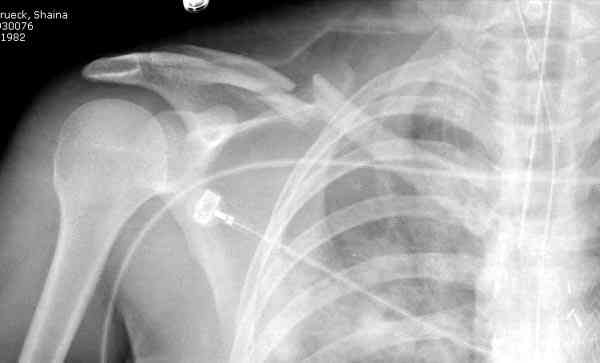

Недавно разбирали случай ложного сустава.

45 летная женщина после автоаварии, алкоголь 163 и 20 летним стажем курения.

Консервативное лечение, через 8 мес. операция Rockwood pin с костной пластикой в нашем городе другим врачом. После 8 недели падение, гвоздь удален оперирующим хирургом, больная направлена к нам. Фиксация реконструктивной пластиной с трикортикальным графтом, добавлен BMP-2. Для стабилизации фиксацию провели через акромион.

Вот уже два месяца больная также продолжает жаловаться на боли, буквально на днях удалили акромиальную часть пластины с специальной пилой с алмазным покрытием для медицинского металла. До сих пор судьба ложного сустава неизвестна....